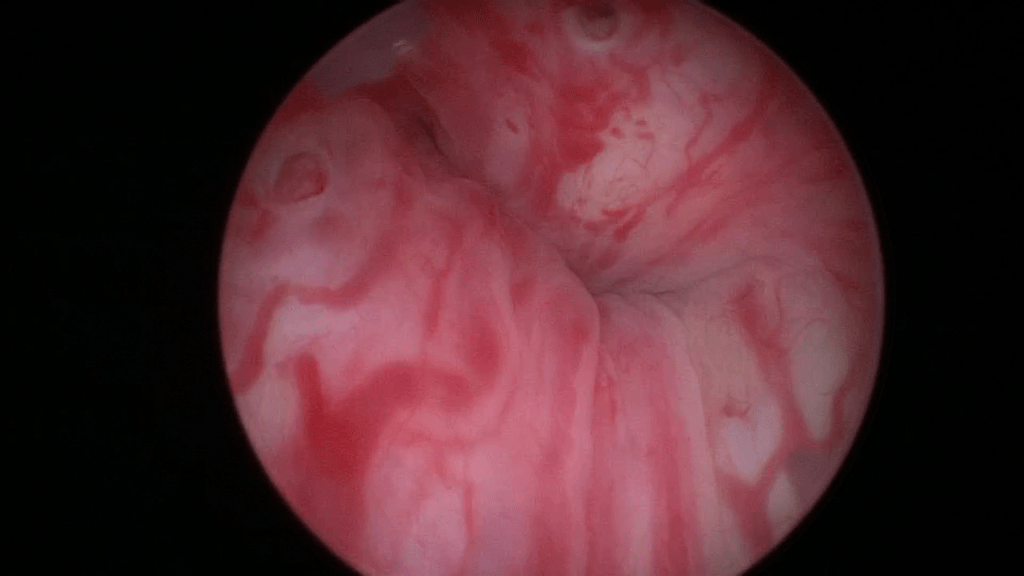

Beginn with a thorough cystoscopy. Patients that have incontinence recurrence should be examined for sling or even suture erosion. Watch out for tumors or stones.

The mid-urethra.